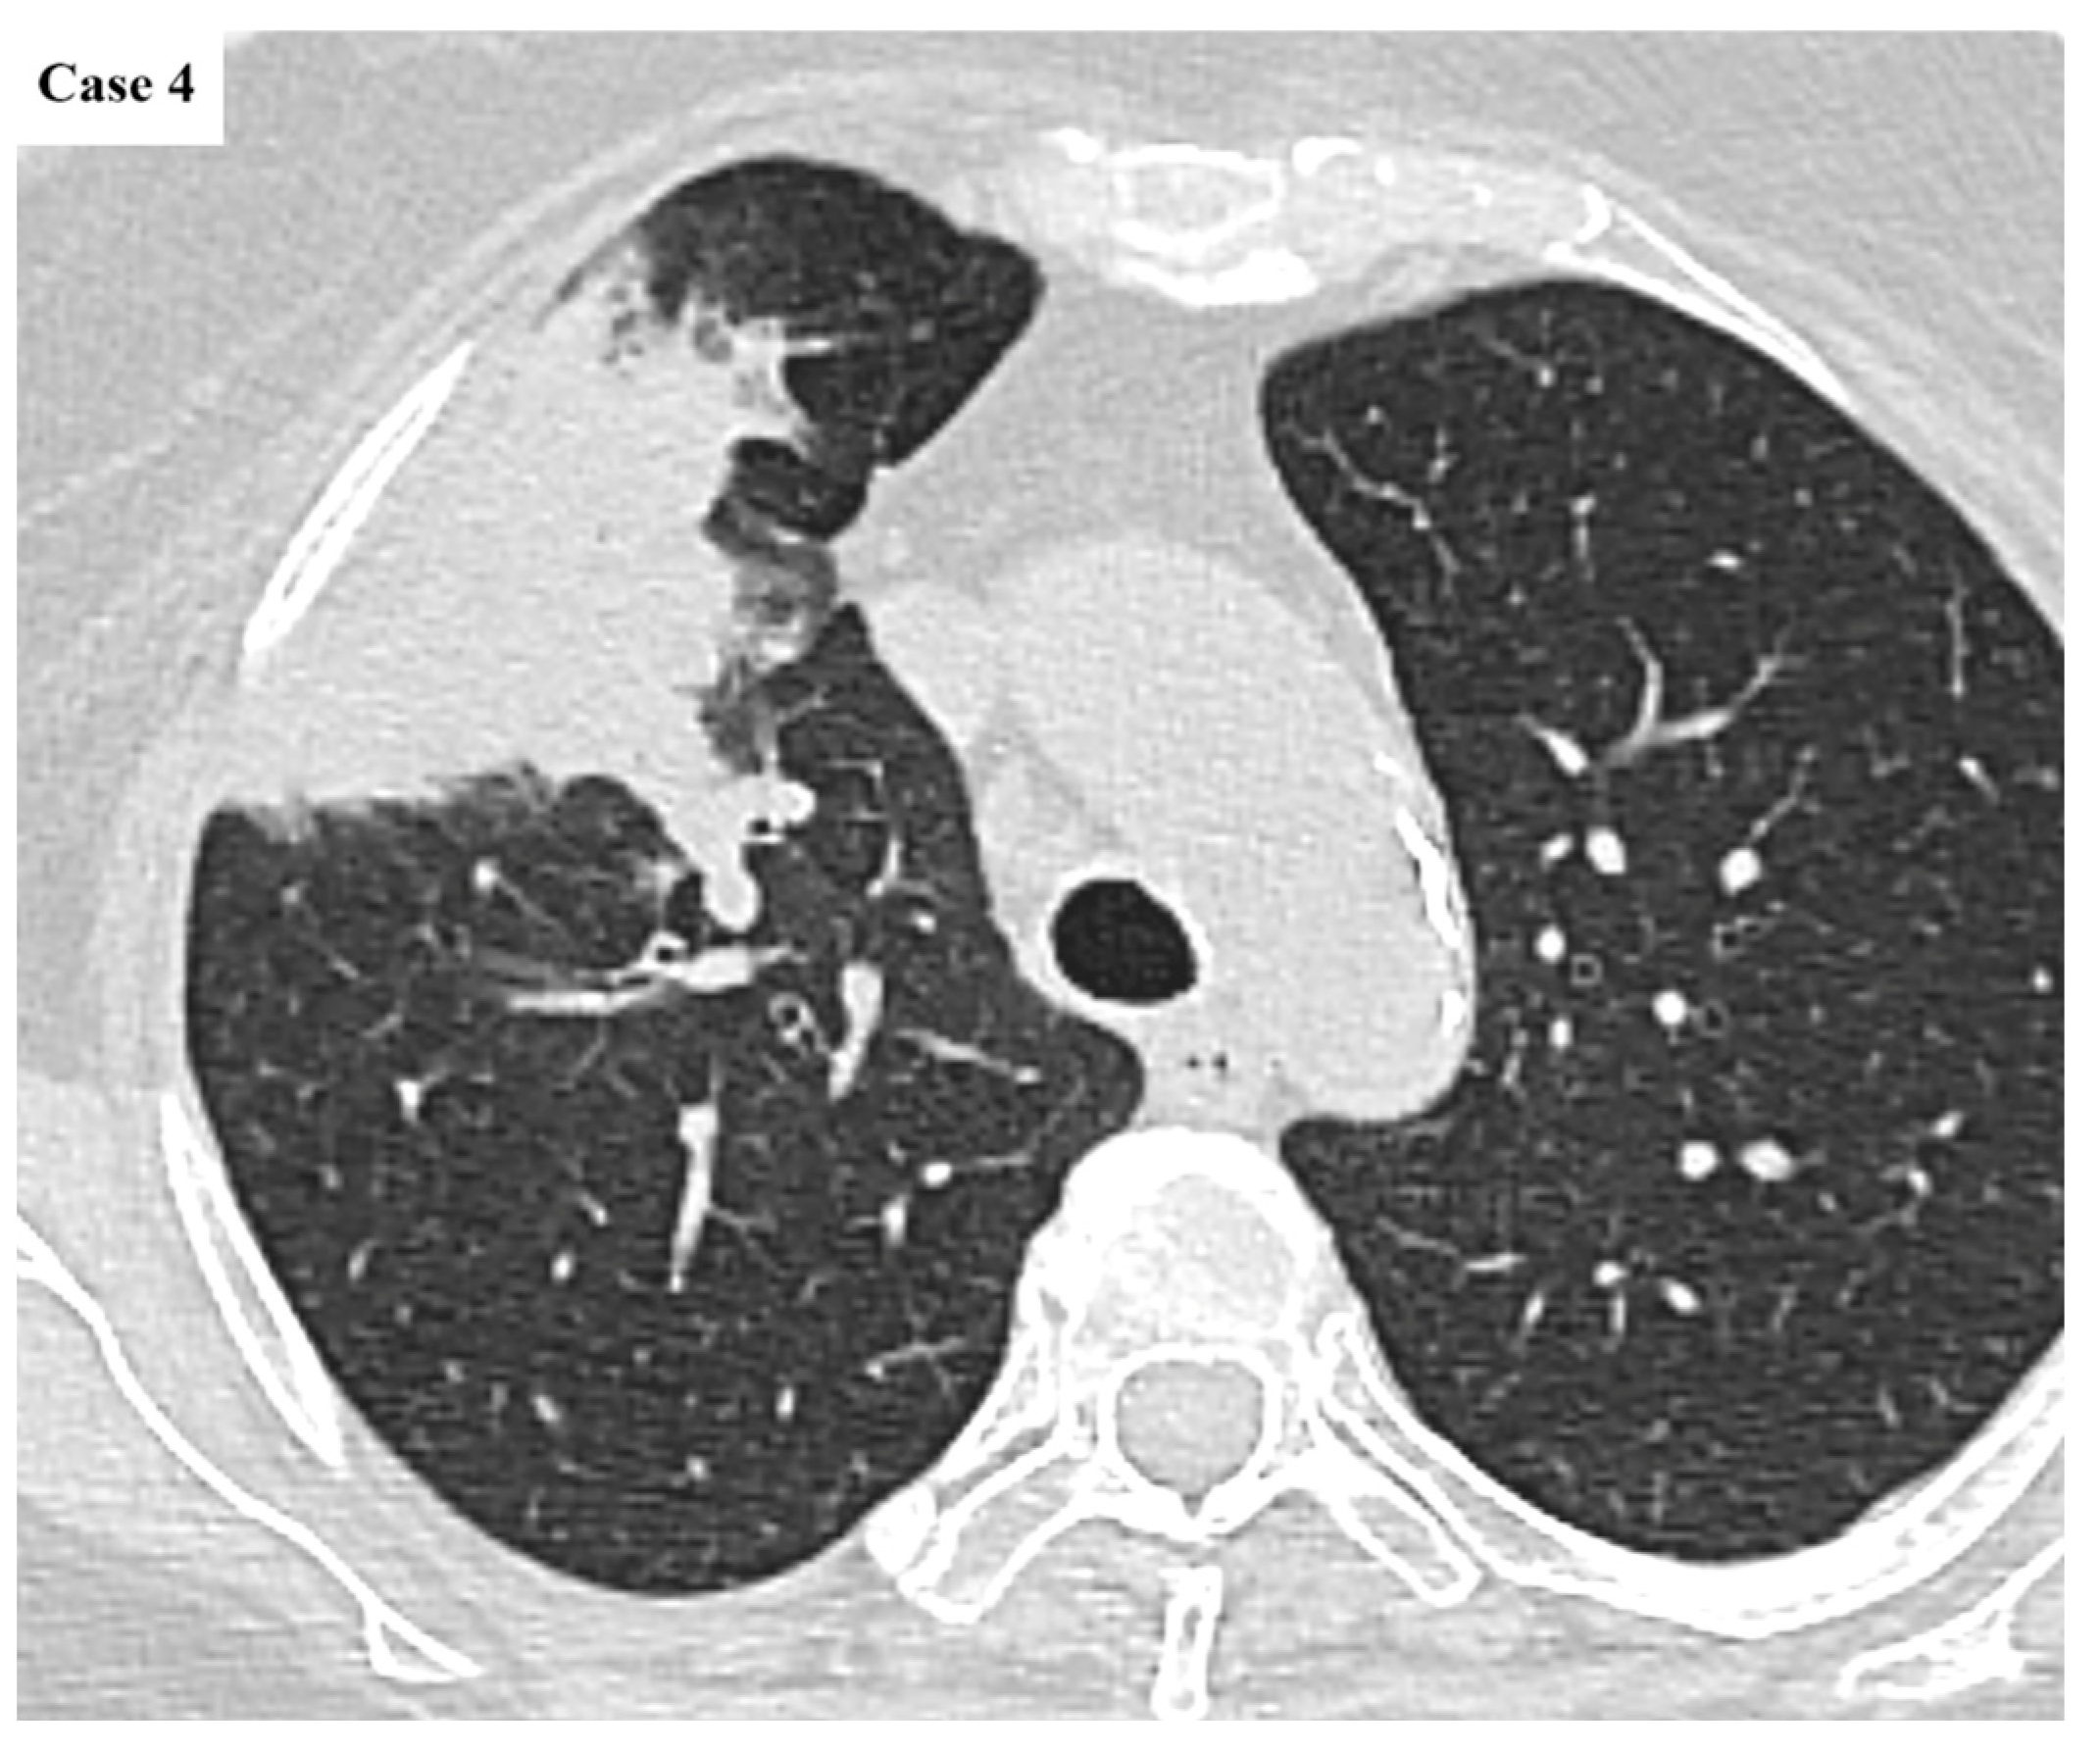

| Imaging features | Spiculated margins: 88% Central necrosis: 38.4% Cavity: 10.4% Lymphangitic spread: 43.2% |